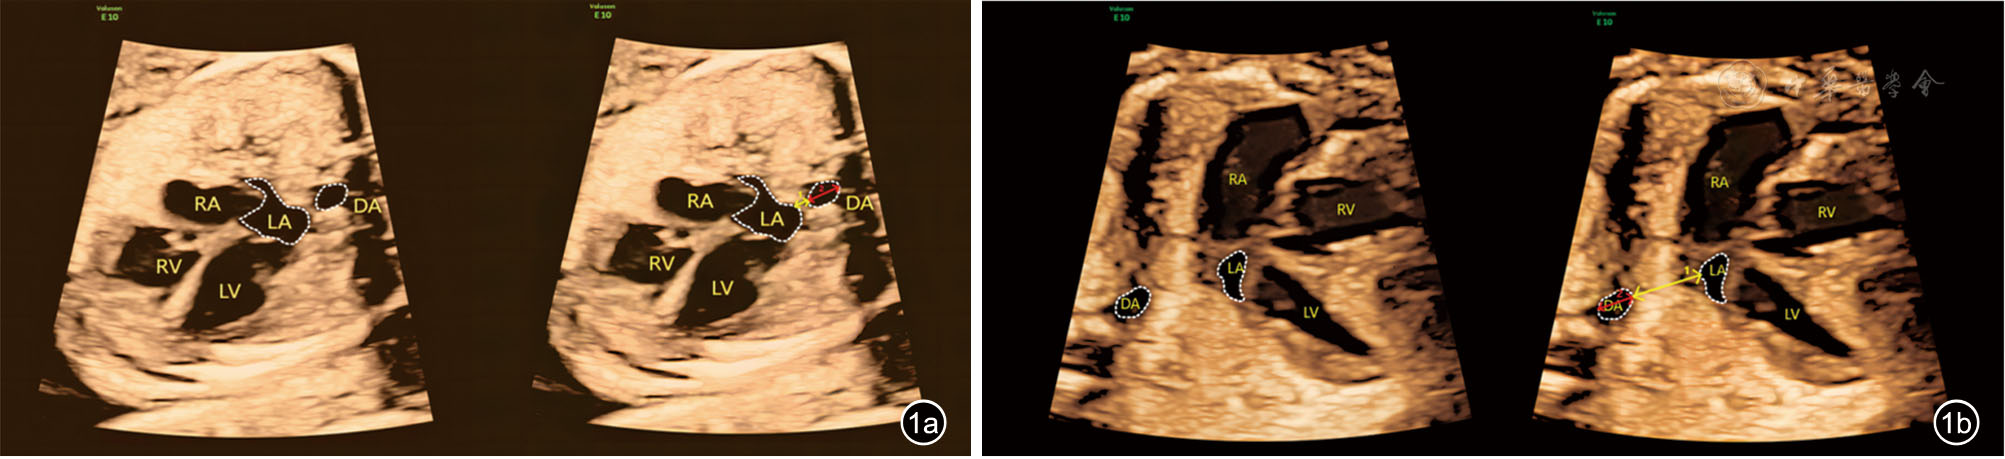

2.测量标准911:在收缩末期的标准四腔心切面,经过胎儿心脏十字交叉和DA的中点画一条线,沿线测量LA后壁外侧缘至DA前壁外侧缘的距离(PLSA)、DA前壁内侧缘至后壁内侧缘的距离(DA内径)。每个参数均测量三次取平均值,单位mm。PLASI=PLSA/DA内径(图1)。

图1 标准四腔心切面左心房后间隙(PLAS)测量超声图像。图a为正常胎儿;图b为肺动脉瓣缺如综合征胎儿[图中黄色线段1为PLAS,红色线段2为降主动脉(DA)内径,左心房后间隙指数(PLASI)=PLAS/DA内径]

注:LA为左心房;LV为左心室;RA为右心房;RV为右心室;DA为降主动脉